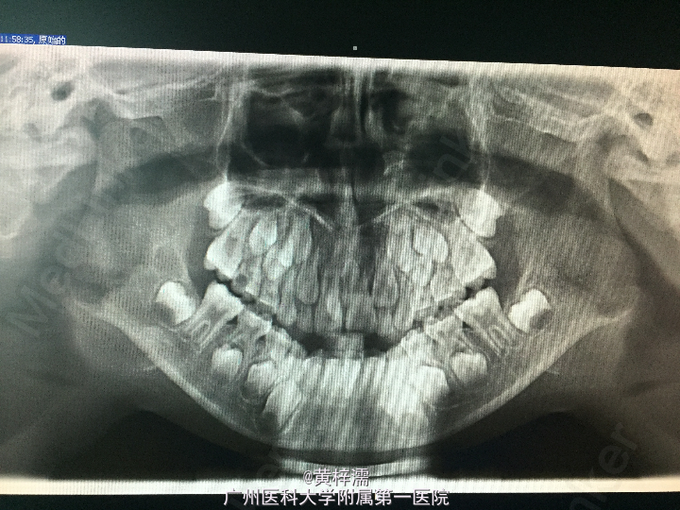

青少年,男性;主诉:检查发现上颌多生牙伴含牙囊肿20余天。患者于外院检查发现多生牙及含牙囊肿,未作处理。

全身检查无特殊。专科检查:口腔卫生可,11、21已萌出,未见牙体病损,无叩痛和松动,牙髓活力正常,11腭侧见白色牙状物,无叩痛和松动。腮腺检查和颌下腺检查未见异常。外院CT提示:符合多生牙,左侧多生牙包埋于囊腔中,囊腔大小为1.5*1.5cm;外院根尖片提示11、21间见多生牙2枚,左侧多生牙冠周见囊性阴影。

诊断:1.上颌埋伏多生牙;2.含牙囊肿。处理:患者入院查体无特殊,行含牙囊肿摘除术+多生牙拔除术,术后予感染、雾化吸入处理。